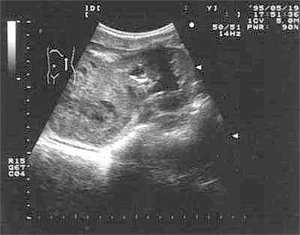

Эхография и РКТ позволяет значительно точнее определить анатомо-топографические и, в какой-то степени, морфологические характеристики нефробластомы (Рис. 1, 2). У всех наших пациентов опухоль была представлена объёмным образованием в виде солитарных масс преимущественно неправильной формы (95,2%). В области опухолевого узла контур почки был выпуклым (14,3%). В 50% обнаруживалась экзофитная зона с фрагментарно выраженной капсулой (71,4%). Эхографическая картина и изображение поражённой почки на РКТ были весьма схожи. Опухоль выглядела как негомогенная структура с преобладанием гиподенситивных очагов (90,5%). Эхографически кальцинаты при нефробластоме выглядят как редкие небольшие высокоинтенсивные сигналы и обнаруживались редко.

Рис. 2. Ультразвуковое сканирование опухоли почки (нефробластома) с очагами распада.